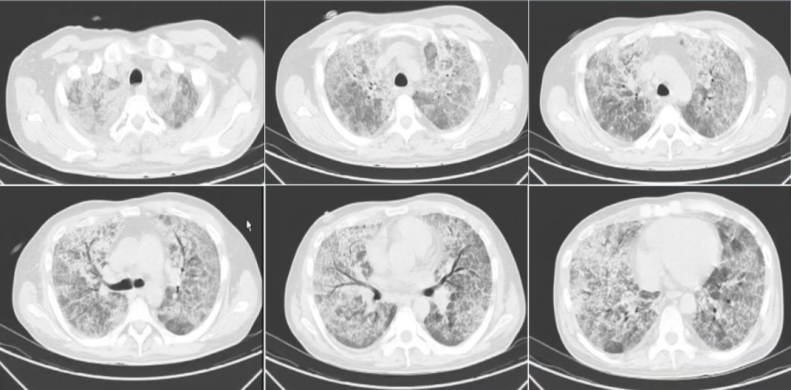

7月15日复查胸部CT:双肺渗出及磨玻璃影较前明显吸收(图3)。患者精神状态及生活质量均得到明显改善。

图片

图3  随访胸部CT(2024-07-15)